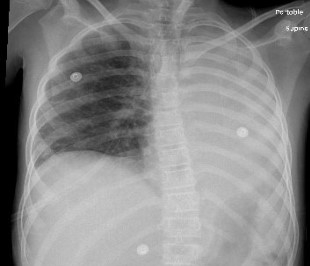

A 9-year-old female with a history of MRSA bacteremia three months ago presented to an outside hospital due to respiratory distress with concerns for pneumonia versus atelectasis. She was transferred to our hospital for escalation of care. On arrival, she had severe left-sided back pain and shortness of breath. Chest x-ray showed complete atelectasis of the left lung (Image 1). Chest CT scan revealed occlusion of the left mainstem bronchus with left mediastinal shift. Echocardiogram was normal. Atelectasis did not improve despite pulmonary clearance regimen (chest physiotherapy, albuterol, hypertonic saline). Reassessment via Chest CT scan revealed a large mycotic pseudoaneurysm that appeared to have a thrombus located in the descending aorta, compressing the left main bronchus and causing atelectasis on the left lung with mediastinal shift (Image 2).

She underwent cardiac catherization, which revealed a large mycotic aneurysm on the descending aorta measuring 18 mm x 15 mm with thrombus around the periphery. The lesion produced a mass effect, compressing the left main bronchus, leading to atelectasis. The pseudoaneurysm was treated via complete coil occlusion to prevent any residual flow to the outpouching sac (Image 3). Following recovery, a repeat chest CT showed improvement of aeration over the left lung field and bronchus.